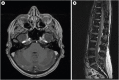

Figures